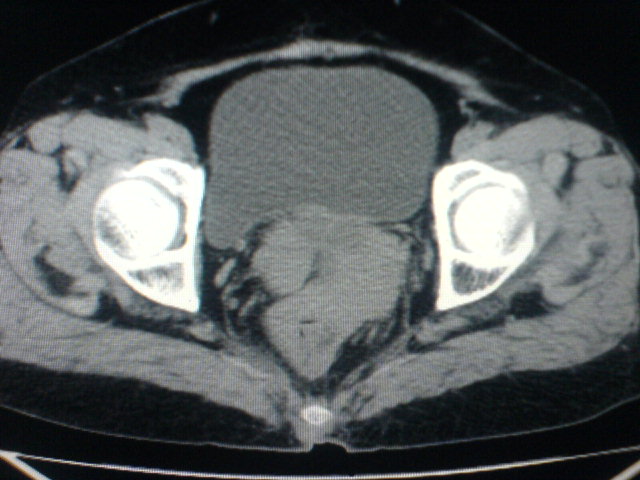

患者为老年女性,肿块最大层面不是位于宫颈,但宫颈偏后方有一囊状低密度影,肿块主要位于乙状结肠及直肠,所以考虑乙状结肠及直肠癌浸犯宫颈可能性大。

患者女性60岁 病史不详

宫颈癌侵犯直肠可能

考虑子宫内膜癌浸犯直肠。

考虑直肠癌侵及宫颈可能;建议增强扫描。

支持考虑宫颈癌上下前后通吃

考虑:直肠及乙状结肠癌侵及宫颈,囊性转移(假性粘液瘤)

支持宫颈癌侵犯直肠。

考虑直肠及乙状结肠癌侵犯邻近结构。